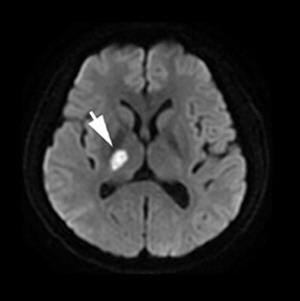

Photo retrieved from Frontiers in Neurology

- Inflammation of nervous system - causes headache, fever, disorientation, poor balance and stroke.